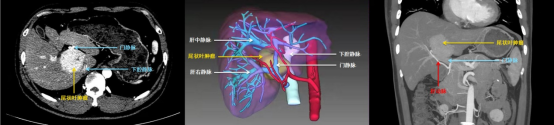

术前影像学、3D立体成像显示,尾状叶肿瘤包绕在肝部大血管中

原来,王先生的肝肿瘤位于肝脏的尾状叶,肝尾状叶曾经一度被称为外科手术的“禁区”,其后方是下腔静脉,前方是左、右肝蒂,上方更是有3支肝静脉包绕,腹腔内最粗的血管几乎都在此处经过,稍有不慎就可能会造成术中大出血,甚至会有死亡的风险。经多方打听,王先生找到陆朝阳,希望能在微创下切除肿瘤。陆朝阳团队发现,王先生的门静脉已经被肿瘤压迫至严重狭窄,如肿物继续增大进一步压迫门静脉,则可能会导致浮肿、腹水、脾大甚至呕血等症状。